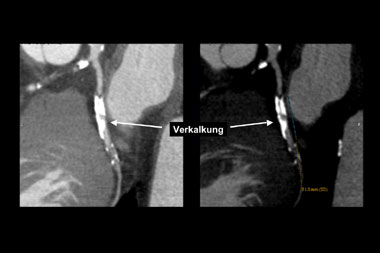

Verkalkungen der Herzkranzgefässe beeinträchtigen aber auch die Darstellung des Lumens in der CT-Angiographie. Bei älteren PatientInnen und solchen mit Diabetes und/oder Niereninsuffizienz, welche ausgeprägte Verkalkungen aufweisen, ist keine schlüssige Beurteilung des Lumens möglich. Zudem kann die EKG-getriggerte Untersuchung bei hoher Herzfrequenz, bei Vorhofflimmern und anderen Rhythmusstörungen, die bei etwa jedem 20. Patienten auftreten, nicht durchgeführt werden. Schliesslich fällt bei Patienten mit schwerer Herzinsuffizienz die Volumenbelastung durch das Kontrastmittel ins Gewicht. Auch durch Stents verursachte Artefakte stellen ein diagnostisches Problem dar (Abbildung 3). Obschon die neuesten CT-Geräte sehr genau die Stentlänge und den Durchmesser erfassen können, ist eine sichere Beurteilung des Lumens in vielen Fällen noch nicht möglich. Da bei der koronaren Herzkrankheit die Frage nach einer Intervention im Vordergrund steht, sei es eine kathetertechnische Stent-Implantation oder eine Bypass-Operation, ist die Erfassung von Koronarstenosen das Hauptziel. Entsprechend ist diese Einschränkung der Aussagekraft der computertomographischen Koronarangiographie durch Gefässwandverkalkungen ein grosser Nachteil dieser Methode. Zusammenfassend ist daher ist der negativ prädiktive Wert der computertomographischen Koronarangiographie sehr hoch. Der positive prädiktive Wert behandlungsbedürftiger Koronarstenosen ist aber beschränkt.

Abbildung 2: Darstellung einer schweren Verkalkung im Ramus circumflexus. Die ausgeprägte Verkalkung verunmöglicht eine korrekte Beurteilung bezüglich Lumeneinengung (links). Mit geeigneten Massnahmen bei der Bildverarbeitung kann dieses Problem teilweise etwas kompensiert werden.